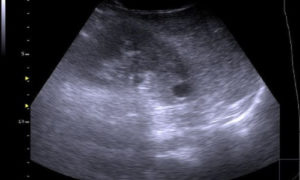

Опять же, наличие в печени эхонегативной структуры говорит о наличии кисты. Простая киста всегда имеет округлую форму и дает тень. Другие варианты таких образований, как правило, требуют дополнительной диагностики.